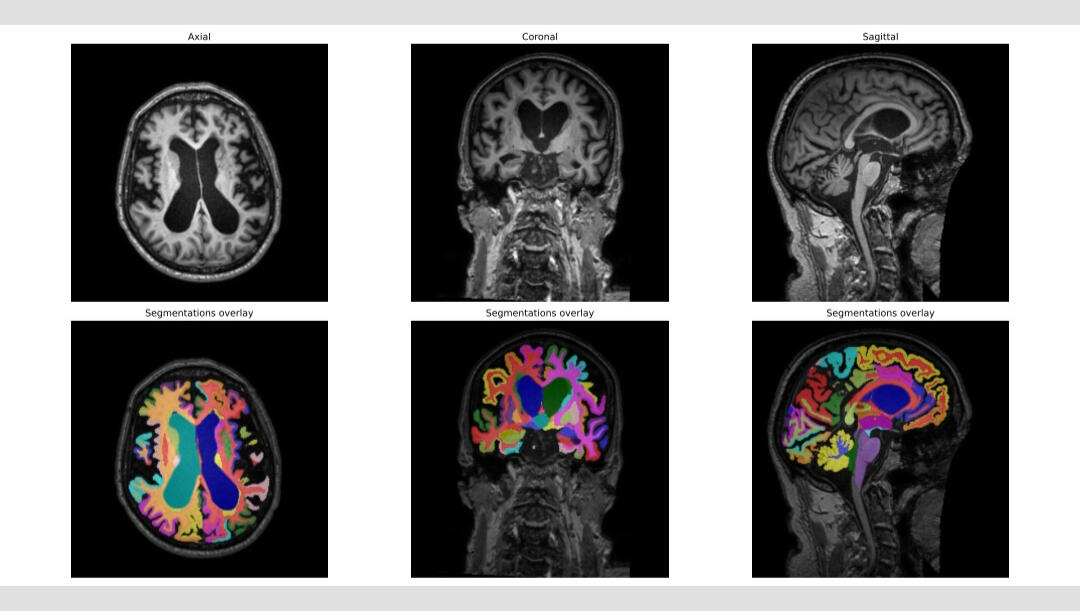

Quantitative Brain Analysis - Dementia Diagnostics

iNPH Diagnostics

Automatic diagnosis of iNPH based on our Deep Learning explainable computer vision model

Automatic diagnosis of iNPH based on our Machine Learning volumetric model

Automatic measurement of Callosal angle (CA), Evans index (EI), 3D EI and cDESH

Automatic diagnosis of iNPH based on our Deep Learning computer vision model